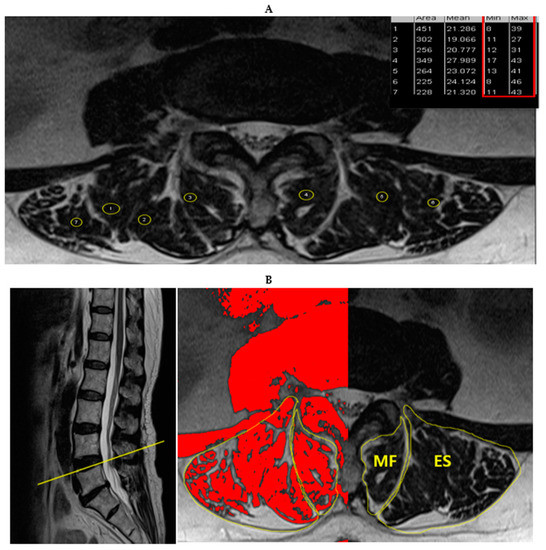

2.2. Measurements and Procedures